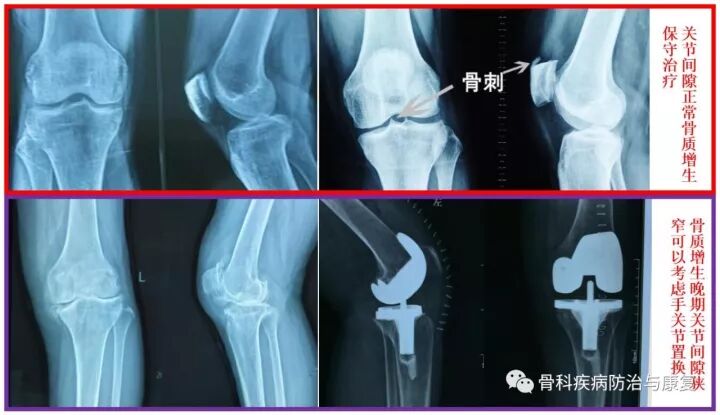

图4膝关节骨质增生X片

膝关节骨质增生:膝关节骨刺大多数情况下是不需要治疗的,尤其膝关节关节面边缘及中间增生的骨刺,只有当骨刺引起关节软骨磨损,或者形成游离体卡主关节的时候,才需要手术治疗,通常情况下,保守治疗即可缓解症状。